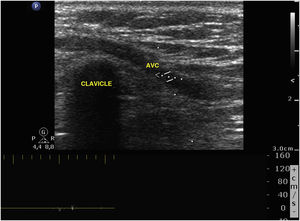

This is the case of a patient admitted to the intensive care unit with signs of right sided pneumonia. A peripherally inserted central catheter (PICC) is cannulated for intravenous treatment. The thoracic x-ray performed reveals that the catheter does not land in the right atrium following a trajectory at clavicle level (Fig. 1). Six days after admission the PICC is removed revealing the presence of neck cellulitis at left jugular vein. The vascular ultrasound performed confirms the presence of venous thrombosis from the cannulation area of the PICC in the mid left cephalic vein (LCV) progressing through the cephalic vein (CV) until it reaches the external jugular vein (EJV) through a segment of supraclavicular anomalous venous communication (AVC) (Figs. 2 and 3).